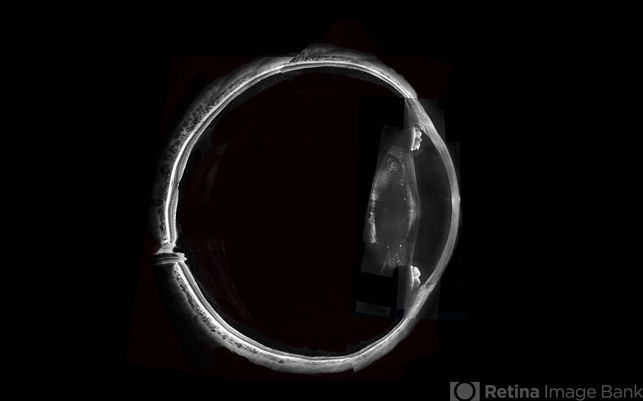

- optical coherence tomography (OCT), swept source, Alports disease

Topcon DRI Triton - Description

- Swept-Source OCT montage of a 45-year-old male with Alports disease and posterior subcapsular cataract.